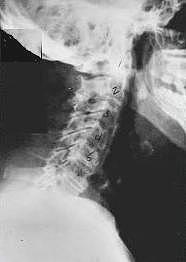

This is a side x-ray view of the neck. As with all the pictures you will see on this page, the patient is looking to the right of the screen, so you are viewing the right side of their neck. We will call this picture a "near normal" spine. Compare this spine with the ones you will see below on this page. Notice the normal forward curve of the neck. This curve helps absorb shock. Notice how each of the disc spaces between C2 (second bone in neck) and C7 are thick and even, this again is normal. Also notice how the front portions (right on the x-ray) of each of the vertebrae (called the 'body' of the vertebrae) are fairly square with clear and well defined borders. This type of arrangement is normal in the neck. Normal vertebrae in other parts of the spine also have similar characteristics to what we see here. When subluxations occur and are left uncorrected, ongoing relentless changes occur that result in damage to the structure and function of the spine along with nerve damage and the resulting problems caused from improper nerve supply.